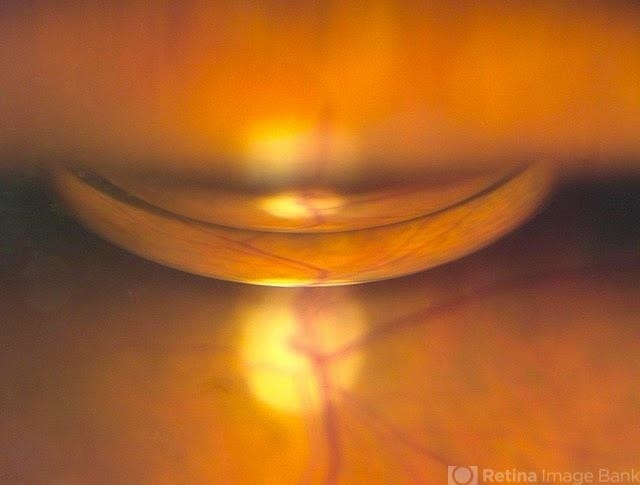

- pneumatic retinopexy

- Patient comes in with retinal detachment and a pneumatic retinopexy was performed. Gas bubble is visible with optic nerve reflected.